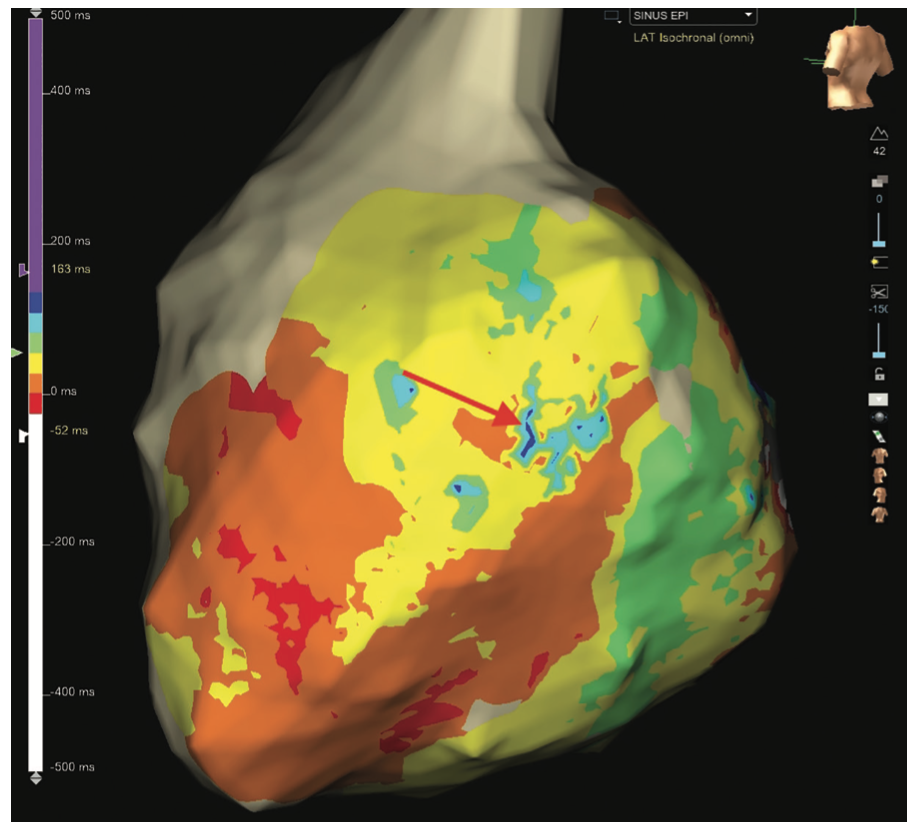

Omnipolar vector maps can highlight areas of rotational activation and slow conduction. The isochronal late activation map (ILAM) can show areas of crowding and deceleration zones, suggestive of entry into diseased channels (Figure 3).